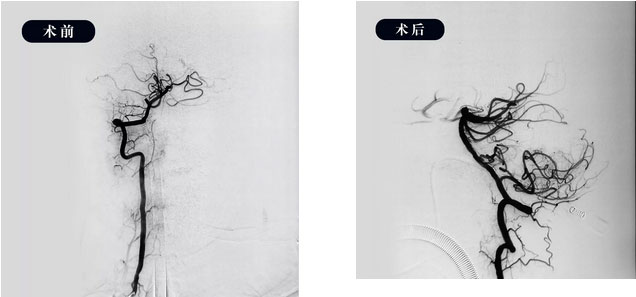

▲ 取栓前后DSA造影图

10:15,在征得家属同意后,患者被送入手术室,全麻下行全脑血管造影示:右侧椎动脉为优势血供动脉,基底动脉起始部闭塞,远端血流受限,必须及时取栓干预。

取栓支架到达血栓处后,开始多次抽吸、支架拉栓,历时两个多小时,取出大量血栓,基底动脉正向血流恢复,双侧大脑后动脉显影良好,达到TICI-III级,完全灌注。复查术后正侧位造影血流正常,即刻床旁CT显示颅内未见出血。